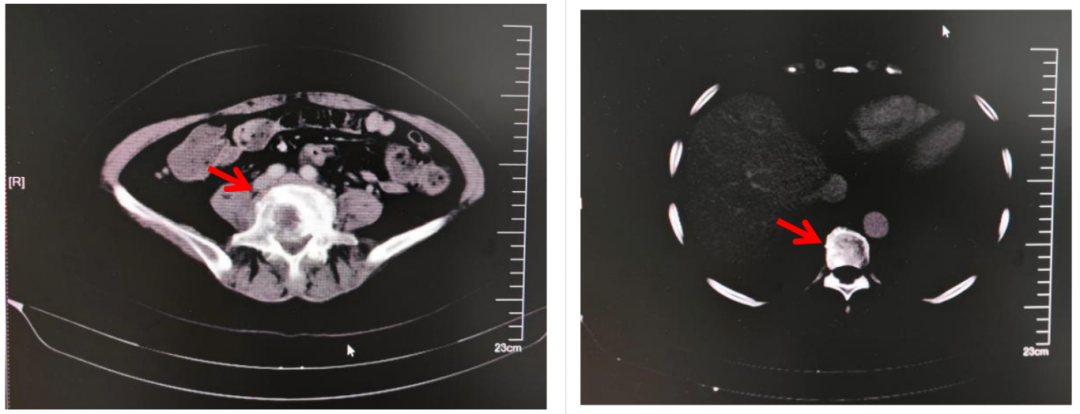

- 机器人辅助半月节电刺激治疗顽固性三叉神经痛1例 三叉神经痛是一种临床常见的面部神经痛,其特征是三叉神经分布的面部区域自发或诱发的电击样痛或刺痛,疼痛较剧烈。2018年头痛疾病国际分类第三版(ICHD-3)将三叉神经痛(TN)分为经典性三叉神经痛、继发性三叉神经痛和特发性三叉神经痛。……